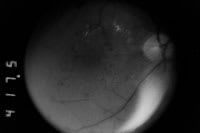

His corrected VA was 20/30 in both eyes. Clinical examination revealed diabetic retinopathy with disc neovascularization in the right eye and 4-quadrant retinal neovascularization and diffuse clinically significant macular edema in both eyes (Figure 2). Following informed consent high-density/low-intensity panretinal and macular SDM was performed for each eye under topical anesthesia in separate sessions.

The patient was lost to follow-up until November 2001 when he returned with corrected VAs of 20/60 right eye and 20/40 left eye. Clinical examination revealed persistent or recurrent diffuse macular edema, some fibrosis of the retinal neovascularization in both eyes, and a preretinal hemorrhage in the left eye. Additional SDM macular photocoagulation was performed December 2001, March 2002, August 2003 (both eyes), and October 2003 (right eye only). Additional panretinal SDM was performed in both eyes December 2001, March 2002, November 2002, and October 2004. During this period of time his macular edema resolved and VA improved. The areas of neovascularization in both eyes demonstrated arrest, arterialization, and fibrosis without contraction, visually significant hemorrhage, or traction retinal detachment. In January 2006 his corrected VA was 20/30 right eye and 20/25 left eye. Intravenous fundus FA revealed persistent leakage from the clinically involutional neovascularization (Figure 2).

Figure 2 C. Preoperative early-phase intravenous fundus fluorescein angiogram, right eye, January 2001. Note early leakage from extensive retinal neovascularization below optic disc. |

|